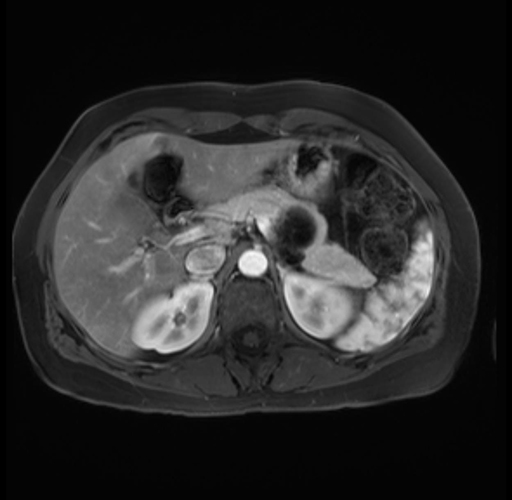

Imaging Analysis

Look through the patient's CT scan to identify any areas of concern for the necessary procedure.

Based on your CT findings, which issue(s) are present and would give reason for "planned slowing down moment(s)" in this case?

Considering a standard distal pancreatectomy procedure, what step(s) of the operation would you do differently in this case?